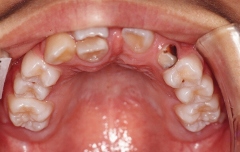

叢生(埋伏歯)

治療前 上顎

乱杭歯及び歯が一本埋伏しています

治療後 正面

正常になっています

治療後 上顎